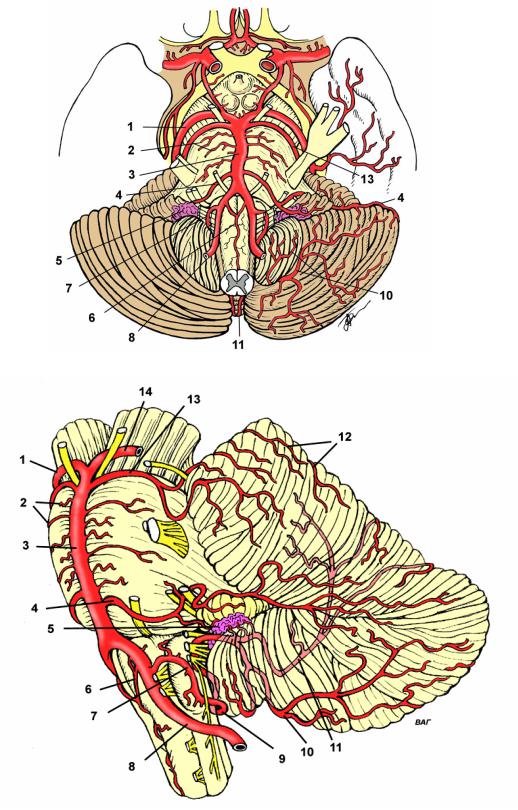

Анатомия: Задняя соединительная артерия мозга